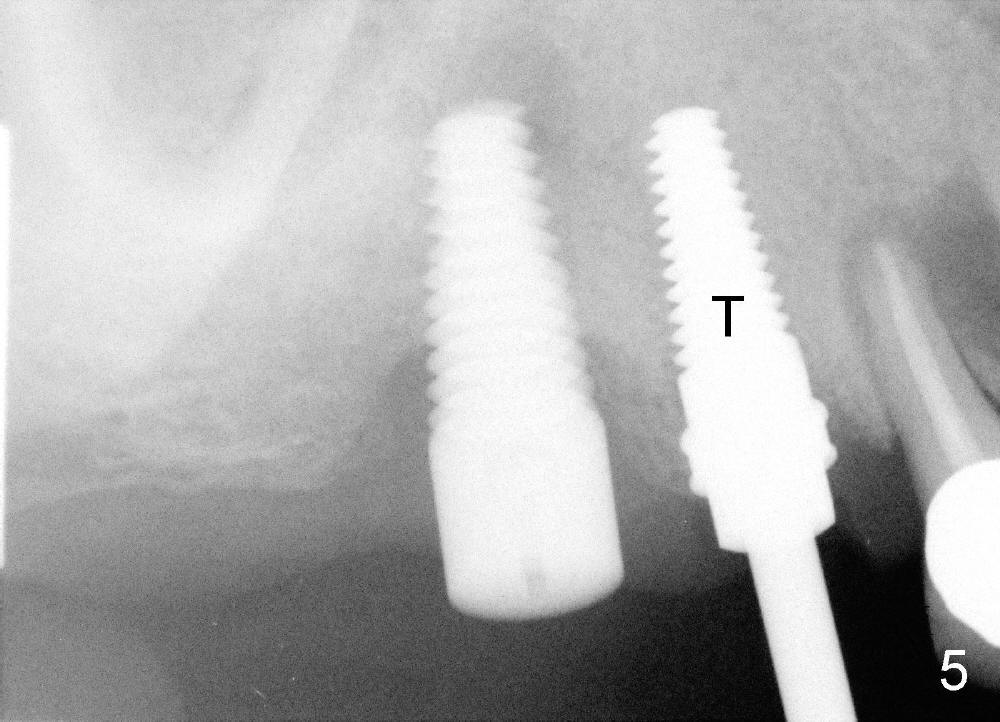

Due to finance, no treatment is provided to #5 (Fig.5 (4.5x14 mm tap),6 (4.5x14 mm implant)). PA (Fig.7) is taken 8 months postop. The crowns at the sites of #3 and 4 have been cemented for 9 months.